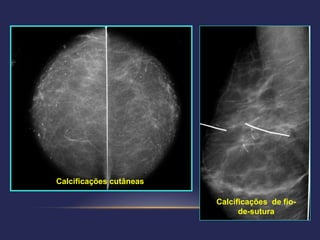

 Categoria 2: achados benignos – seguimento: rotina

   linfonodos intramamários          calcificações cutâneas

simples após ultra-sonografia     calcificações de fios de sutura

Calcificações cutâneas

Calcificações de fio-

de-sutura